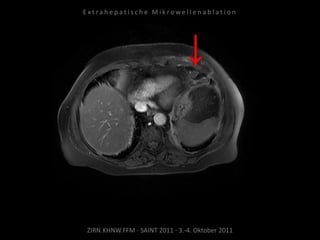

Bildgebung vor MWA:

CT 17.02.2010

Ablation am 04.03.2010:

3 Nadelpositionen.

Verlaufskontrolle:

MRT 09.04.2010

CT 24.06.2010

Regredienz des abladierten

Tumorgewebes.

CT 15.09.2010

Weitere Regredienz des abladierten

Resultat:

Abladierte Lymphknotenmetastasen

deutlich regredient, Gefahr für die

verbliebene Niere gebannt.